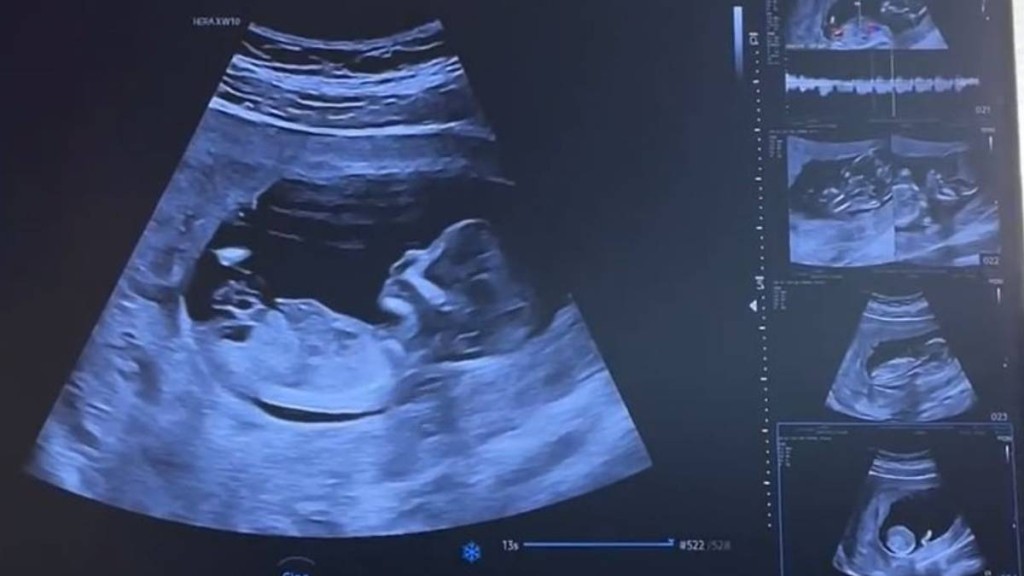

多地提高產檢報銷 退休人員受惠引熱議

為應對人口挑戰,內地持續加大鼓勵生育的政策力度。踏入2026年,北京、寧夏、福州等多地相繼宣布,大幅提高產前檢查費用的報銷水平。其中最引人注目的是,北京市的新政策將退休人員的產檢醫療費用也納入報銷範圍,此舉在網絡上引發廣泛討論。不少網民對此感到驚訝,紛紛留言調侃:「沒有看錯吧,退休人員還有產檢啊?」、「這是把(生育)這個任務交給退休人員了嗎?」。有評論則指出,此政策是為了讓「失獨家庭」的高齡產婦也能享受到產檢報銷福利。由於她們退休後勞動關係終止,不再被生育保險覆蓋,新政正是對這類複雜社會需求的具體回應。

具體而言,北京市參加生育保險的女職工,其產前檢查費用報銷上限由原來的最高3000元人民幣,大幅提升至3000元以內100%報銷,超過3000元的部分則可報銷30%,基金最高支付額達到1萬元。而廣東惠州、福建福州等地更為進取,率先推出了女職工產前檢查政策內費用全額報銷的政策。浙江省則實施了「生育服務包」全額保障政策,參保人可享受每周期3450元的產前檢查服務包,每多生育一胎還可額外增加1000元。